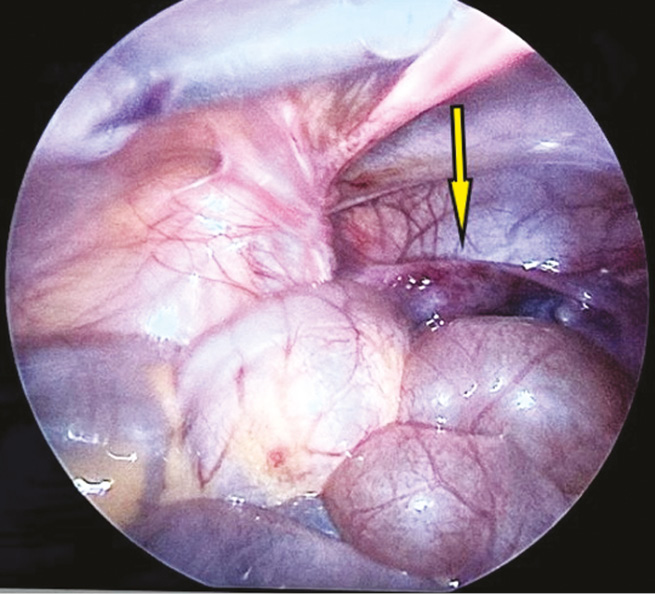

In the analysis of the case histories of the patients, preoperative transabdominal ultrasonography showed the uterus deviating toward ovary torsion in one patient. Based on this data, we determined the position of the uterus in girls who underwent laparoscopic surgery for nongynecologic abdominal pathology. Consequently, left-sided lateroflexion of the uterus was detected in a 10-year-old girl who underwent surgery for destructive appendicitis (Fig. 6).

Fig. 6. Endoscopic view during revision of the pelvic organs. The arrow points to the left-sided lateroflexion of the uterus

Рис. 6. Эндоскопическая картина при ревизии органов малого таза. Стрелка указывает на левостороннюю латерофлексию матки

Postoperatively, transabdominal ultrasonography and MRI were performed to examine the pelvic organs. However, echography data did not provide any useful information. Conversely, MRI confirmed the presence of uterine lateroflexion (Fig. 7).